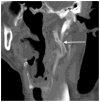

Eagle syndrome is a rare condition resulting from elongation of the temporal styloid process or calcification of its associated stylohyoid ligaments. Although usually presenting with pain or odynophagia, Eagle syndrome has been reported to cause a multitude of neurologic symptoms or vascular complications, some of which can be life-threatening. We present a case in which an endovascularly placed internal carotid artery stent in close proximity to a calcified stylohyoid ligament resulted in stent fracture with subsequent stent and vessel occlusion. We review and discuss the presentation, diagnosis, etiology, complications and treatment options of the syndrome.